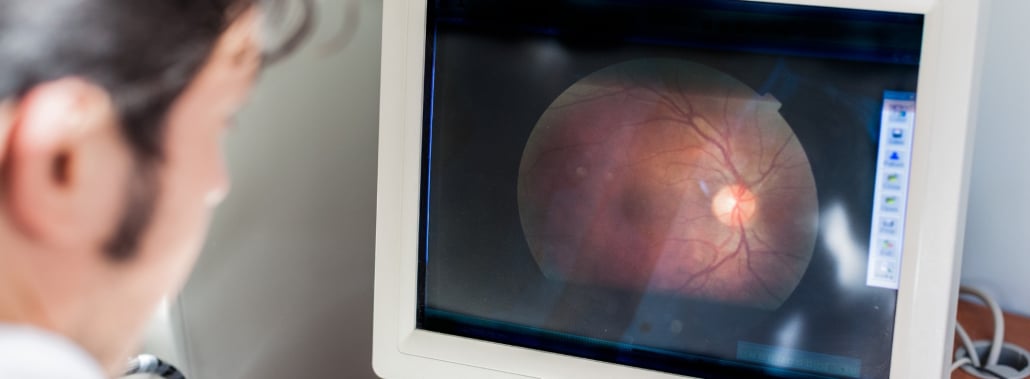

La Amaurosis Congénita de Leber (LCA) es una enfermedad rara, hereditaria y devastadora, que provoca una pérdida severa de visión desde los primeros meses de vida. Aunque durante años se consideró un diagnóstico sin opciones, los avances en genética han cambiado por completo el panorama: hoy es posible identificar el gen causante, anticipar complicaciones y, en algunos casos, optar a terapias innovadoras como la terapia génica.

La Amaurosis Congénita de Leber es un grupo de enfermedades hereditarias de la retina que causan una pérdida visual grave desde el nacimiento o durante los primeros meses de vida. Afecta aproximadamente a 1 de cada 30.000 a 80.000 recién nacidos.